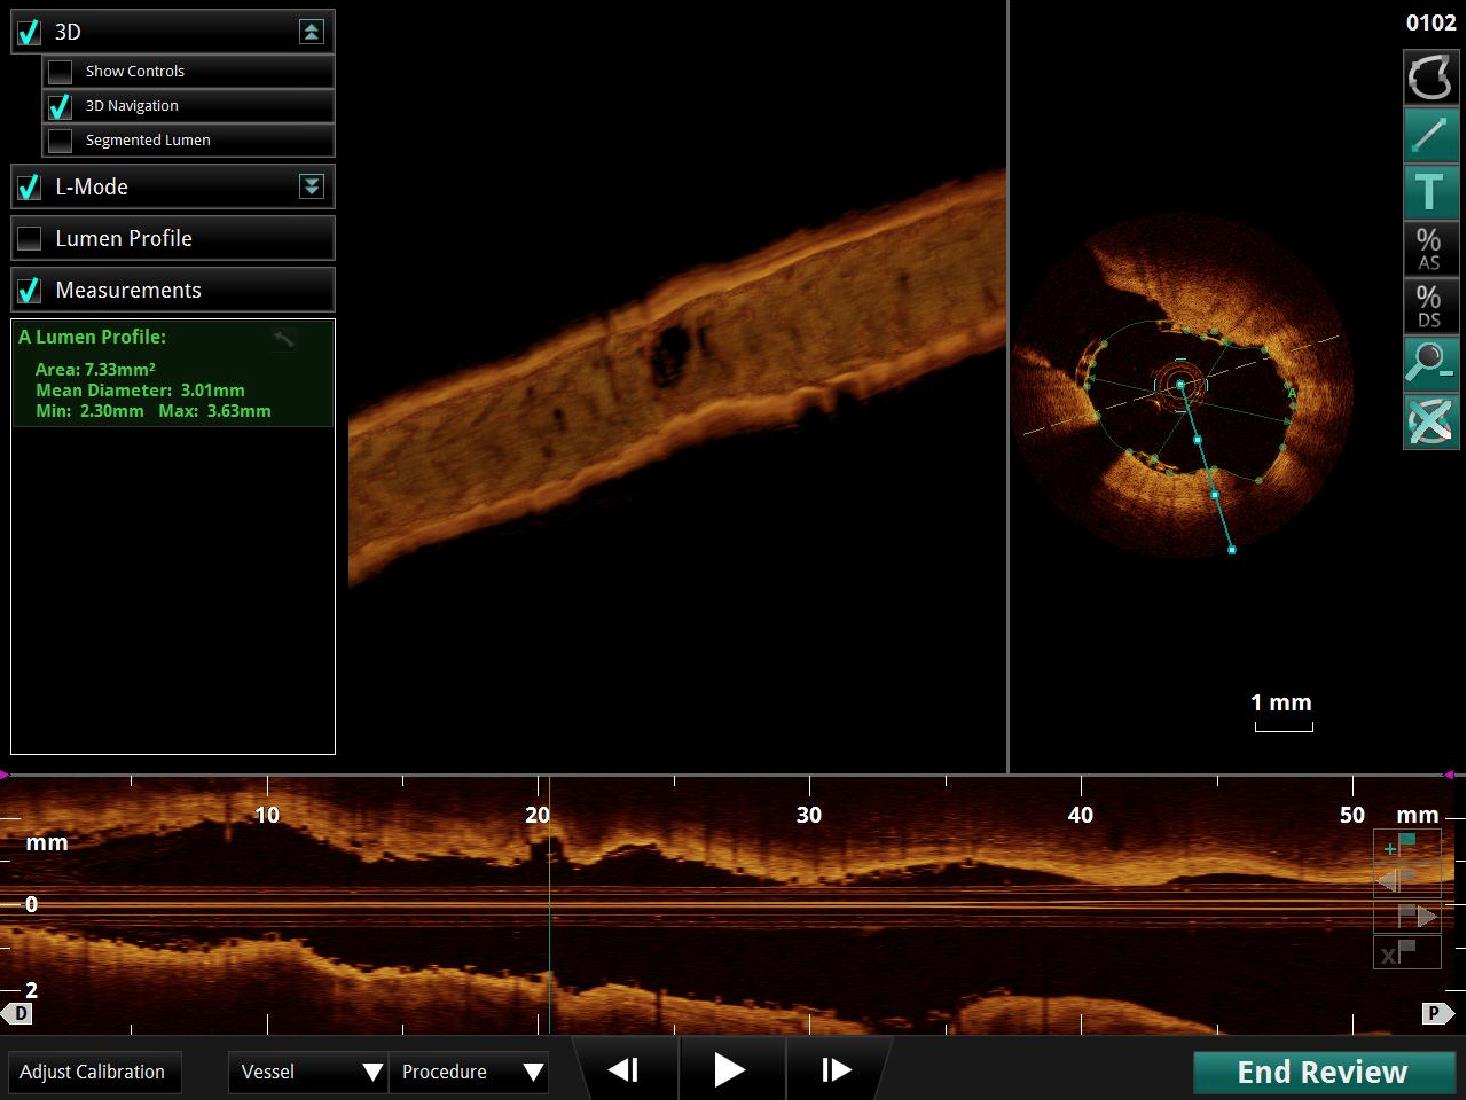

Die optische Kohärenztomographie (OCT) ist ein weiteres invasives bildgebendes Verfahren in der Diagnostik der koronaren Herzerkrankung. Auf Infrarotlicht basierend, ist eine hohe Auflösung biologischer Gewebestrukturen und hierdurch eine optimale und suffiziente Bildgebung der koronaren Gefäßwand möglich.

Durch die OCT können Koronarplaque mit höherer Sensivität und Spezifität erkannt und deren Beschaffenheit interpretiert werden. Durch die hohe Auflösung der OCT können im Besonderen komplexe Bifurkationsstenosen, Stenosen des Hauptstamms, oder Stenosen an mehreren Koronararterien beurteilt werden. Auch die Beurteilung der Lage und Positionierung eines Stents ist nach Implantation in hoher bildlicher Auflösung möglich und ist hier von besonderer Bedeutung.

Neuerdings wird in der Medizinischen Klinik I am Universitätsklinikum Gießen die neuartige dreidimensionale - Echtzeitdarstellung der OCT eingesetzt. Hierdurch werden 360°-Panoramaansichten des Gefäßes möglich und die Stentimplantation kann noch präziser geplant und optimiert werden. Die 3-D OCT Rekonstruktion ermöglicht eine besonders realitätsnahe 3D-Darstellung der Koronararterien.